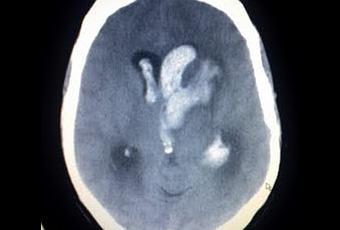

Ok maintenant, qu'on a grossièrement défini l'AVC, voyons à quoi il ressemble:

Honnêtement, ça vous fout les boules, une pathologie qui ressemble à un bonhomme qui sourit??D'où il vient?

L'AVC survient de deux manière différente soit par une artère du cerveau qui se bouche à cause d'un caillot, soit l'artère explose carrément sous l'effet d'une pression trop importante. En terme technique on dit que l'AVC est soit ischémique soit hémorragique.

Source photo: Wikipedia